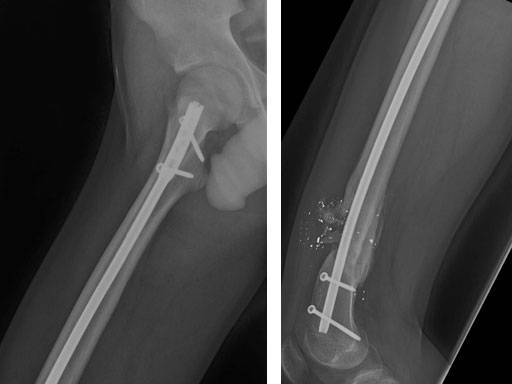

Fig 3ab AP x-rays 6 months postoperatively.

Fig 3cd Lateral x-rays 6 months postoperatively.